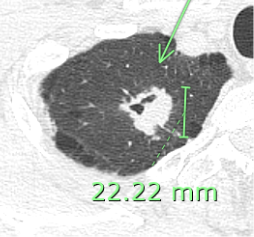

(スピキュラ(ギザギザ) 胸膜陥入(引き込み)のCT画像)

●縁がギザギザしている(スピキュラ)

白いしこりの形に注目。ボールのように丸くツルッとしているのではなく、縁から外側に向かってトゲのようなものが伸び、ギザギザしているのが分かります。 これは、がん細胞が周囲の組織へじわじわと浸透(浸潤)して広がろうとしている様子を示しています。

●肺の膜を引っ張っている(胸膜陥入像)

緑色の矢印が指している部分をご覧ください。 しこりと胸壁(肺の外側の壁)の間が、糸で引っ張られたようにくびれているのが分かります。 これは、がん細胞が増殖する過程で周囲の組織を巻き込み、収縮するために起こる現象です。肺の表面を覆う膜(胸膜)を内側に引き込んでしまっている状態です。

結果的には進行した肺腺がんでした